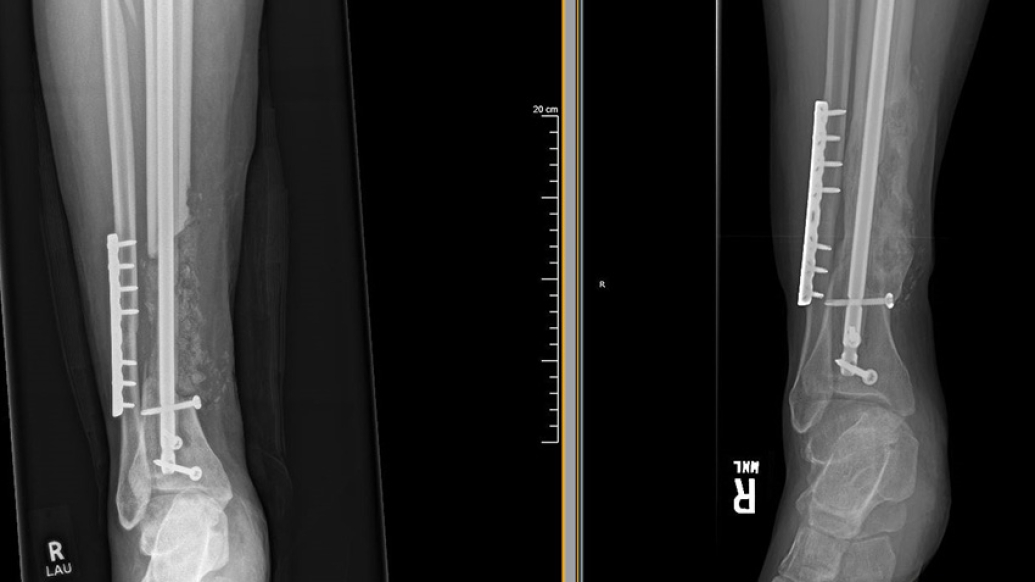

X-rays from a patient with an open tibia fracture. The X-ray on the right shows how the bone has now filled in following the surgical technique.